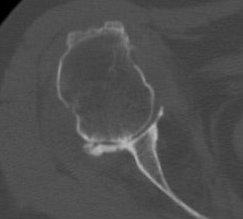

Walch classification glenoid morphology

Type A - centred humeral head, concentric wear, no humeral head subluxation

A1: minor central erosion

A2: major central erosion with humeral head protrusion

Type B - posterior subluxation of the humeral head, with biconcave glenoid and asymmetric wear

B1: narrowing of the posterior joint space

B2: biconcave glenoid with posterior rim erosion and retroverted glenoid

B3: monoconcave glenoid with > 15° retroversion or >70% posterior humeral head subluxation or both

Type C

C1: dysplastic glenoid with >25° retroversion

C2: biconcave, posterior bone loss, posterior translation of the humeral head

Type D: glenoid anteversion or anterior humeral head subluxation <40°

Type A2 Type B1

Type B2 Type B3

Type B3